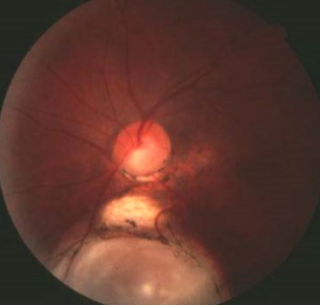

morning glory syndrome

etiology: variant of ON/central coloboma, variant of ON dysplasia

very rare

usually unilateral

females > males

systemic abnormalities:

basal encephalocele

hypertelorism + wide head, flat nose, midline notch in upper lip

CNS vascular anomalies

appearance:

larger than normal ONH

funnel-shape conical excavation

irregular pigmented PPA

white glial tissue at its base

unusual vascular pattern

vessels radiate from periphery of disc

abnormally straight

increased #

difficult to differentiate arterioles from venules

complications:

VA may be normal but often worse than 20/200

associated VF defects & severe decreased VA

r/o systemic abnormalities w/ neurological consult

at risk for non-rhegmatogenous RD